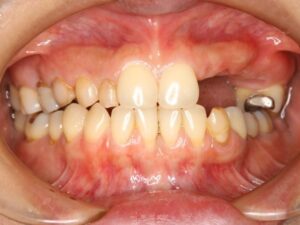

初めての来院時

初めて来院した時は、「上顎左側の歯が欠損した部分に新しく入れ歯を作ったが、違和感が大きくて、この先長く使っていられるものではなく、不安が大きくなり相談に来ました」との事でした。

この方の場合は、上顎の前歯と奥歯の間の永久歯が左右各4本ずつ先天的に欠如し、乳歯が晩期残存していました。

上の写真の上顎の左側の葉の欠損部分は、大学病院で乳歯を抜歯後に、一般的な保険の入れ歯を作ってもらったそうですが、「とてもはめていられない」との事でした。

写真の上顎右側の中間の歯も4本が乳歯の晩期残存で、永久歯が先天的に欠如し、乳歯の歯根は殆ど残っておらず、歯がグラグラの状態で、保存不可能だった為、上顎右側の4本の乳歯も抜歯との診断になりました。